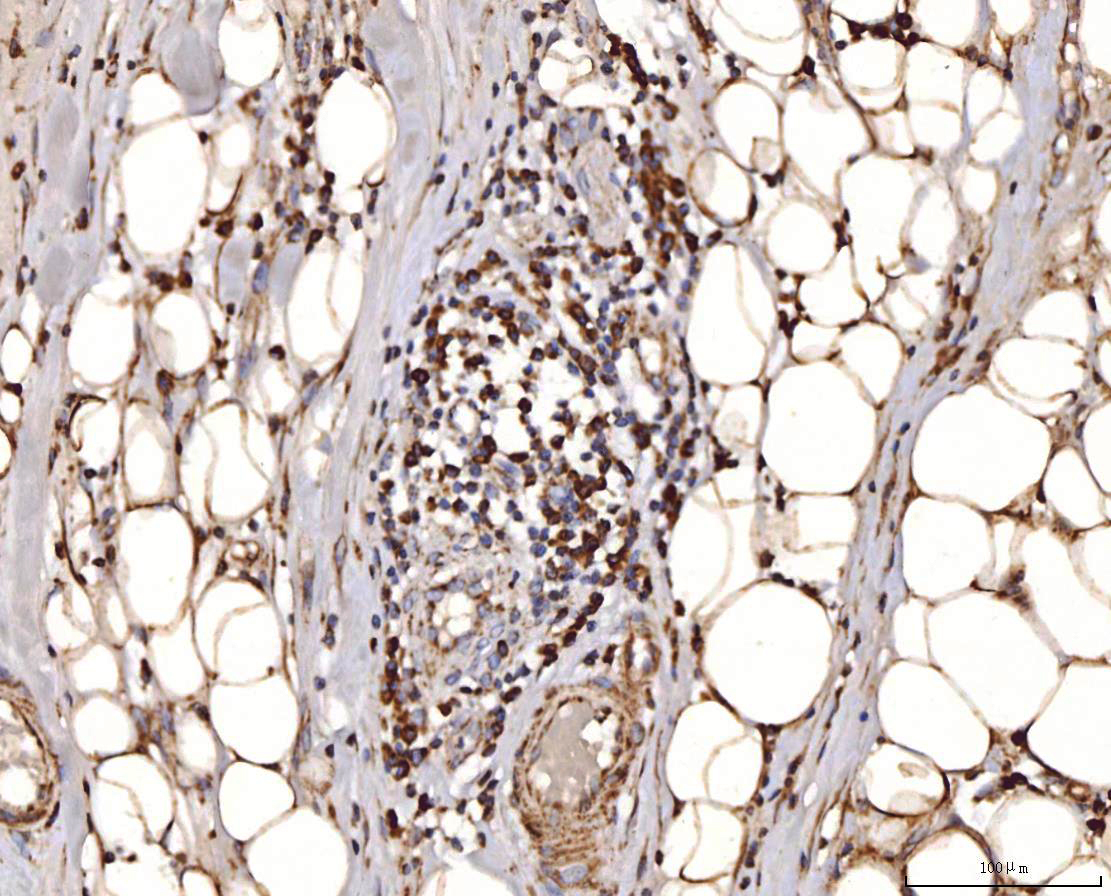

IHC analysis of COX4I1 using anti-COX4I1 antibody (A05442-2).

COX4I1 was detected in a paraffin-embedded section of human liver cancer tissue. Biotinylated goat anti-rabbit IgG was used as secondary antibody. The tissue section was incubated with rabbit anti-COX4I1 Antibody (A05442-2) at a dilution of 1:200 and developed using Strepavidin-Biotin-Complex (SABC) (Catalog # SA1022) with DAB (Catalog # AR1027) as the chromogen.